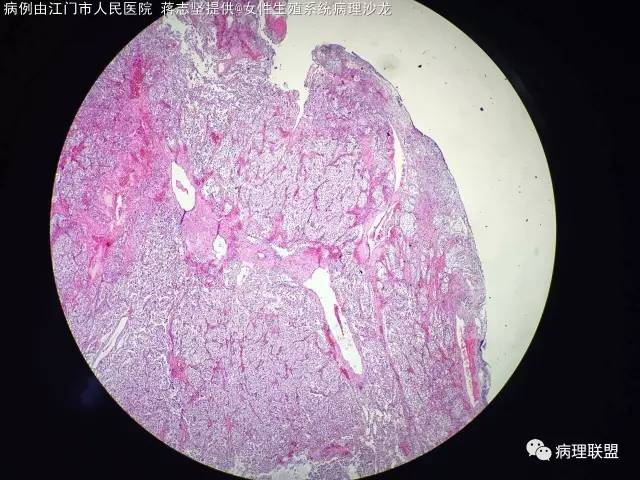

女,20岁,宫腔赘生物,子宫下段后壁2×1×1cm,HCG 不高,一年前卵巢手术,病理,浆液性囊性腺纤维瘤,本次宫腔镜手术(病例由江门市人民医院 蒋志坚提供,致谢!)